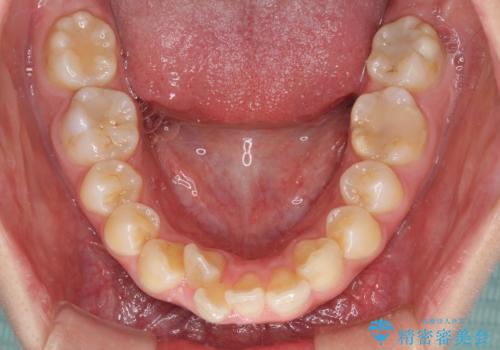

- 上の前歯の出っ歯とでこぼこの歯並びを気にして来院された患者様です。

口元を積極的に引っ込めるために、上下左右の小臼歯4本を抜歯することとしました。